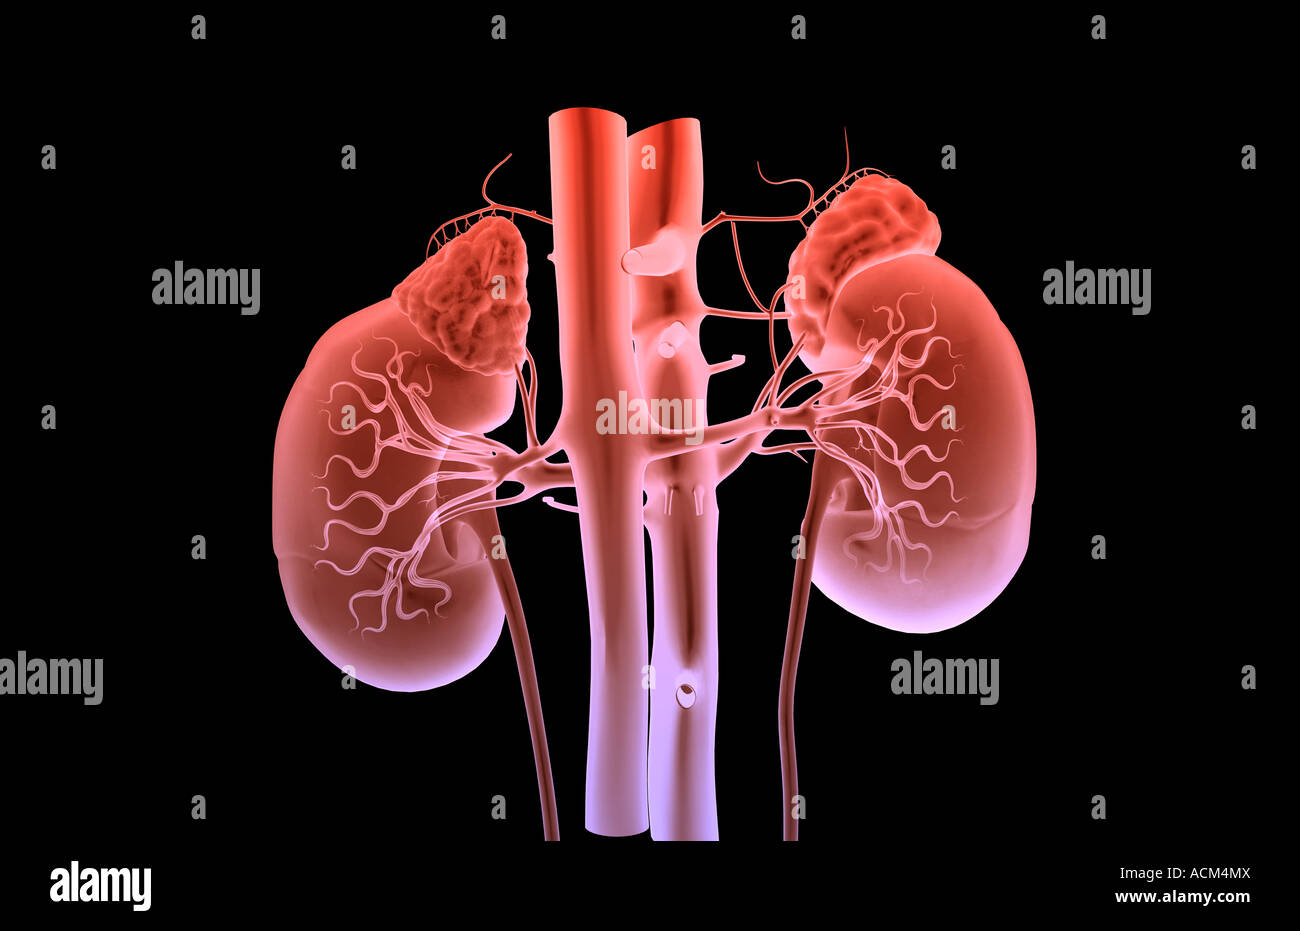

RF2X8JJJR–Die 3D-Darreichungsform von Krebs erfordert eine Blutversorgung, um die Nährstoffe und den Sauerstoff zu liefern, die sie zum Wachstum und Überleben benötigt

RF2X8JJJT–Die 3D-Darreichungsform von Krebs erfordert eine Blutversorgung, um die Nährstoffe und den Sauerstoff zu liefern, die sie zum Wachstum und Überleben benötigt

RF2X8JJJX–Die 3D-Darreichungsform von Krebs erfordert eine Blutversorgung, um die Nährstoffe und den Sauerstoff zu liefern, die sie zum Wachstum und Überleben benötigt